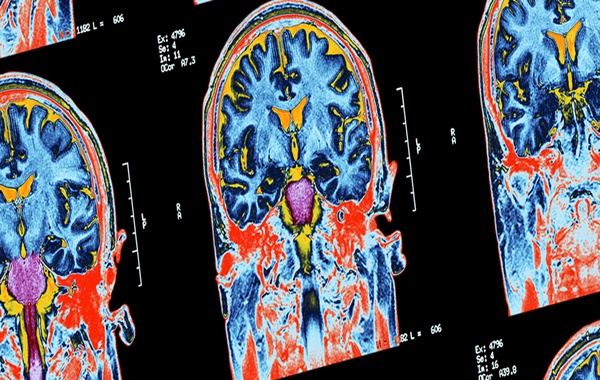

In the new study, signs of consciousness were found through fMRI (functional magnetic resonance imaging) and EEG (electroencephalography) brain scans in 60 out of 241 patients tested, after being given instructions such as “imagine opening and closing your hand”.

“However, when they are assessed with advanced techniques such as task-based fMRI and EEG, we can detect brain activity that suggests otherwise.